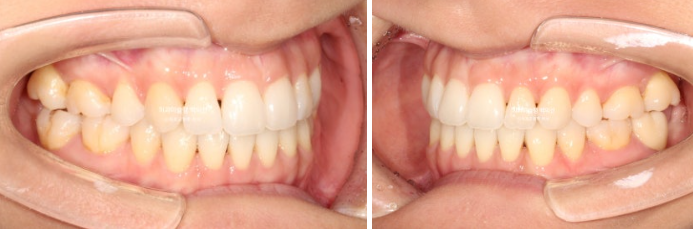

25년 2월 교정치료를 위해 온 환자분입니다.

오래 전 발치교정을 했는데 유지관리 단계에서 다시 틀어져 버렸습니다.

재교정을 해서 고치고 싶은 것은 튀어나온 위 앞니와 아래앞니의 블랙트라이앵글

앞니 하나가 들려있어요.

중절치 하나가 많이 나와있습니다.

아랫니도 약간의 배열 불규칙이 보입니다.